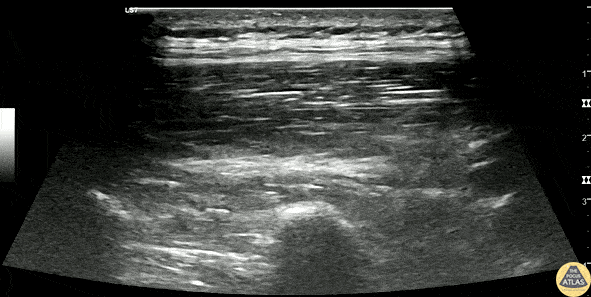

30s M PMH chronic pancreatitis presented with epigastric pain, failing conservative management and continuing to have breakthrough pain on his home PO opiates. He was scheduled to have a celiac plexus neurolysis later in the month with interventional radiology but presented for uncontrolled pain. He had been given multiple doses of IV opioids in ED without effective pain control. An US guided erector spinae plane block was performed as shown. The needle is seen entering in-plane with a probe placed in the sagittal plane, and advanced until touching the transverse process (*), and injecting anesthetic within the fascial plane between the transverse process and the erector spinae muscles. The patient had effective control of pain and was able to be discharged home. Dr. Nhu-Nguyen Le, Fellow Denver Health Ultrasound Fellowship